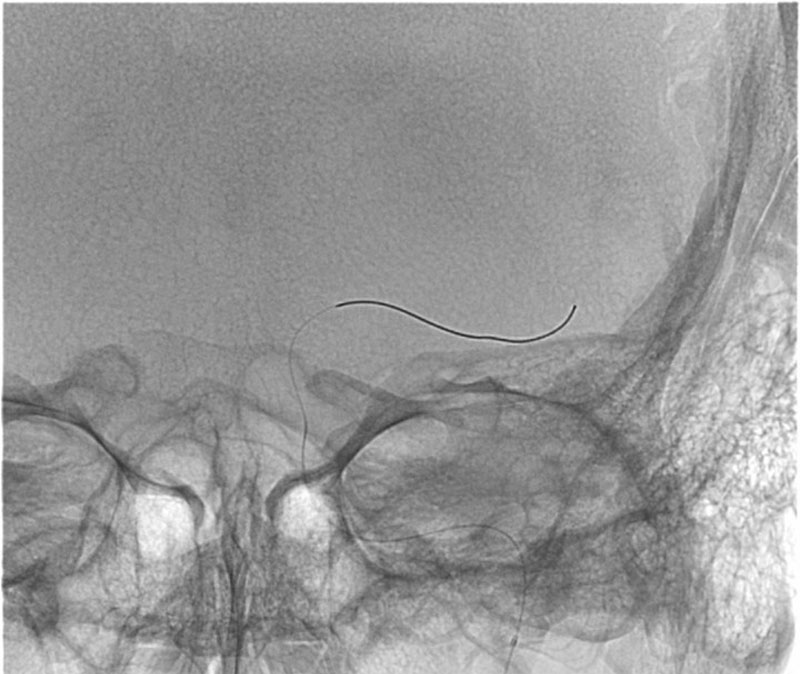

ICA-M1 intracranial dissection EVT

This clinical case presents a 28-year-old female patient presenting with a wake-up stroke, managed with endovascular treatment.

• 28 yo, Female

• Wake up stroke (LKW 02.00)

• NIHSS: 15

• No i.v. lysis

• CTA: 10.25

• Groin puncture: 11.07

DSA